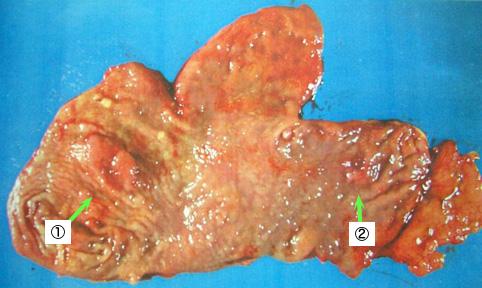

症例提示(所在地,施設名等): 福岡県・ 国家公務員共済組合連合会 浜の町病院 (松浦隆志先生からの提供症例)

疾患(病理主体)の分類良性上皮性腫瘍/腺腫

部位(臓器別)胃(部位)/2つ以上

検査方法マクロ

病変の最大径(ミリ)20〜24

多発腫瘍(同一臓器)有(同時性)